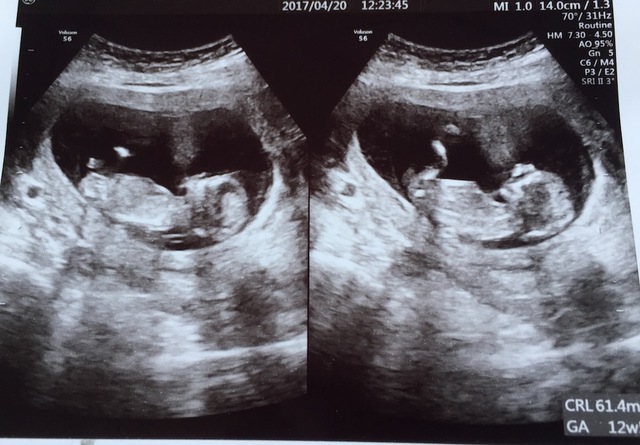

12週6日(12w6d・性別不明・双子)|ちびのすけ さん(37歳)

エコー写真撮影時のエピソード:

およそ1ヶ月前に双子と診断されて初めは戸惑って不安に陥ったけど、今はパパと息子とツインズが生まれて来てくれるのを心待ちにしています。

両親は思いもよらない報告にびっくりしてますが、まずは無事に産まれてきてくれることを願ってくれてます。